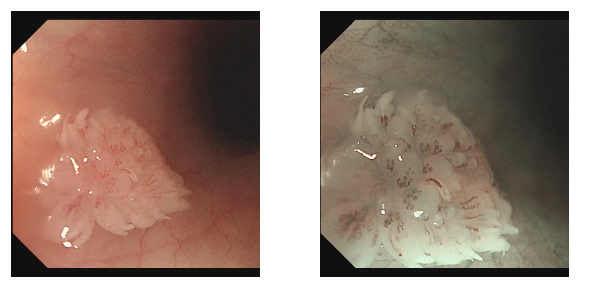

检查过程中,内镜医生有了意外发现:小张的食管部位长有一个形似花朵的乳头状瘤。吕主任介绍,食管乳头状瘤在临床中并不常见,尤其是在年轻男性群体中更为少见,其发病多与病毒感染相关,比如HPV病毒。幸运的是,发现及时,肿瘤尚处于早期阶段,医生随即为小张进行了内镜下切除术,整个过程顺利完成。